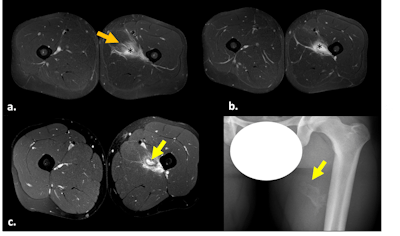

Fat-suppressed T2-weighted (a,b) and fat-suppressed proton density-weighted (c) axial images. Myotendinous injury at the mid/distal aspect of the insertion of the adductor longus, with hematoma (black asterisks) and surrounding edema (orange arrow), which corresponds to British Athletics Muscle Injury Classification (BAMIC) 2b injury. Follow-up MRI (c) and x-ray (d) depicted a pseudonodular lesion with a surrounding hypointense halo (c) within the previous affected area, related to the evolution of ossifying myositis. All images courtesy of Dr. Pablo Vargas Avila et al, Hospital Universitario 12 de Octubre, Madrid, and presented at ECR 2024.